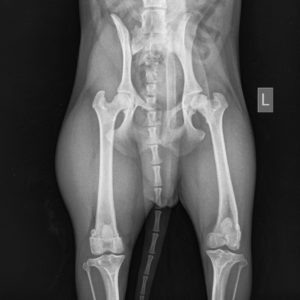

Инструментальные методы включают в себя рентгенографию тазобедренного сустава, артроскопию, компьютерную томографию, УЗИ тазобедренного сустава.

Асептический некроз головки бедра

Тяжелая форма болезни Пертеса